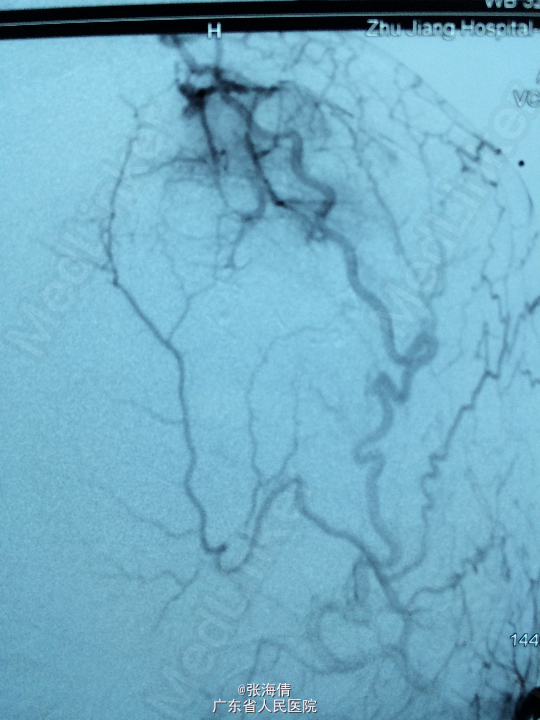

诊断:脑膜瘤 处理:先予DSA以明确肿瘤供血情况,术中脑膜瘤供血丰富,用PVA颗粒超选到供血动脉将其闭塞。后再择期在气管全麻下行脑膜瘤切除术。

术后病理提示:脑膜瘤,WHO I级,瘤组织浸润脑组织。免疫组化:Ki一67(<1%)(+),CK(一),GFAP(一),Vimentin(+),EMA(+),P53(一),ER(一),PR(一)。 讨论:脑膜瘤首选方法为手术切除,手术切除脑膜瘤是最有效的治疗手段,但是由于其供血经常较为丰富,故可先行介入栓塞供血动脉后再行切除,这样可以降低手术风险和手术难度,改善患者手术预后。